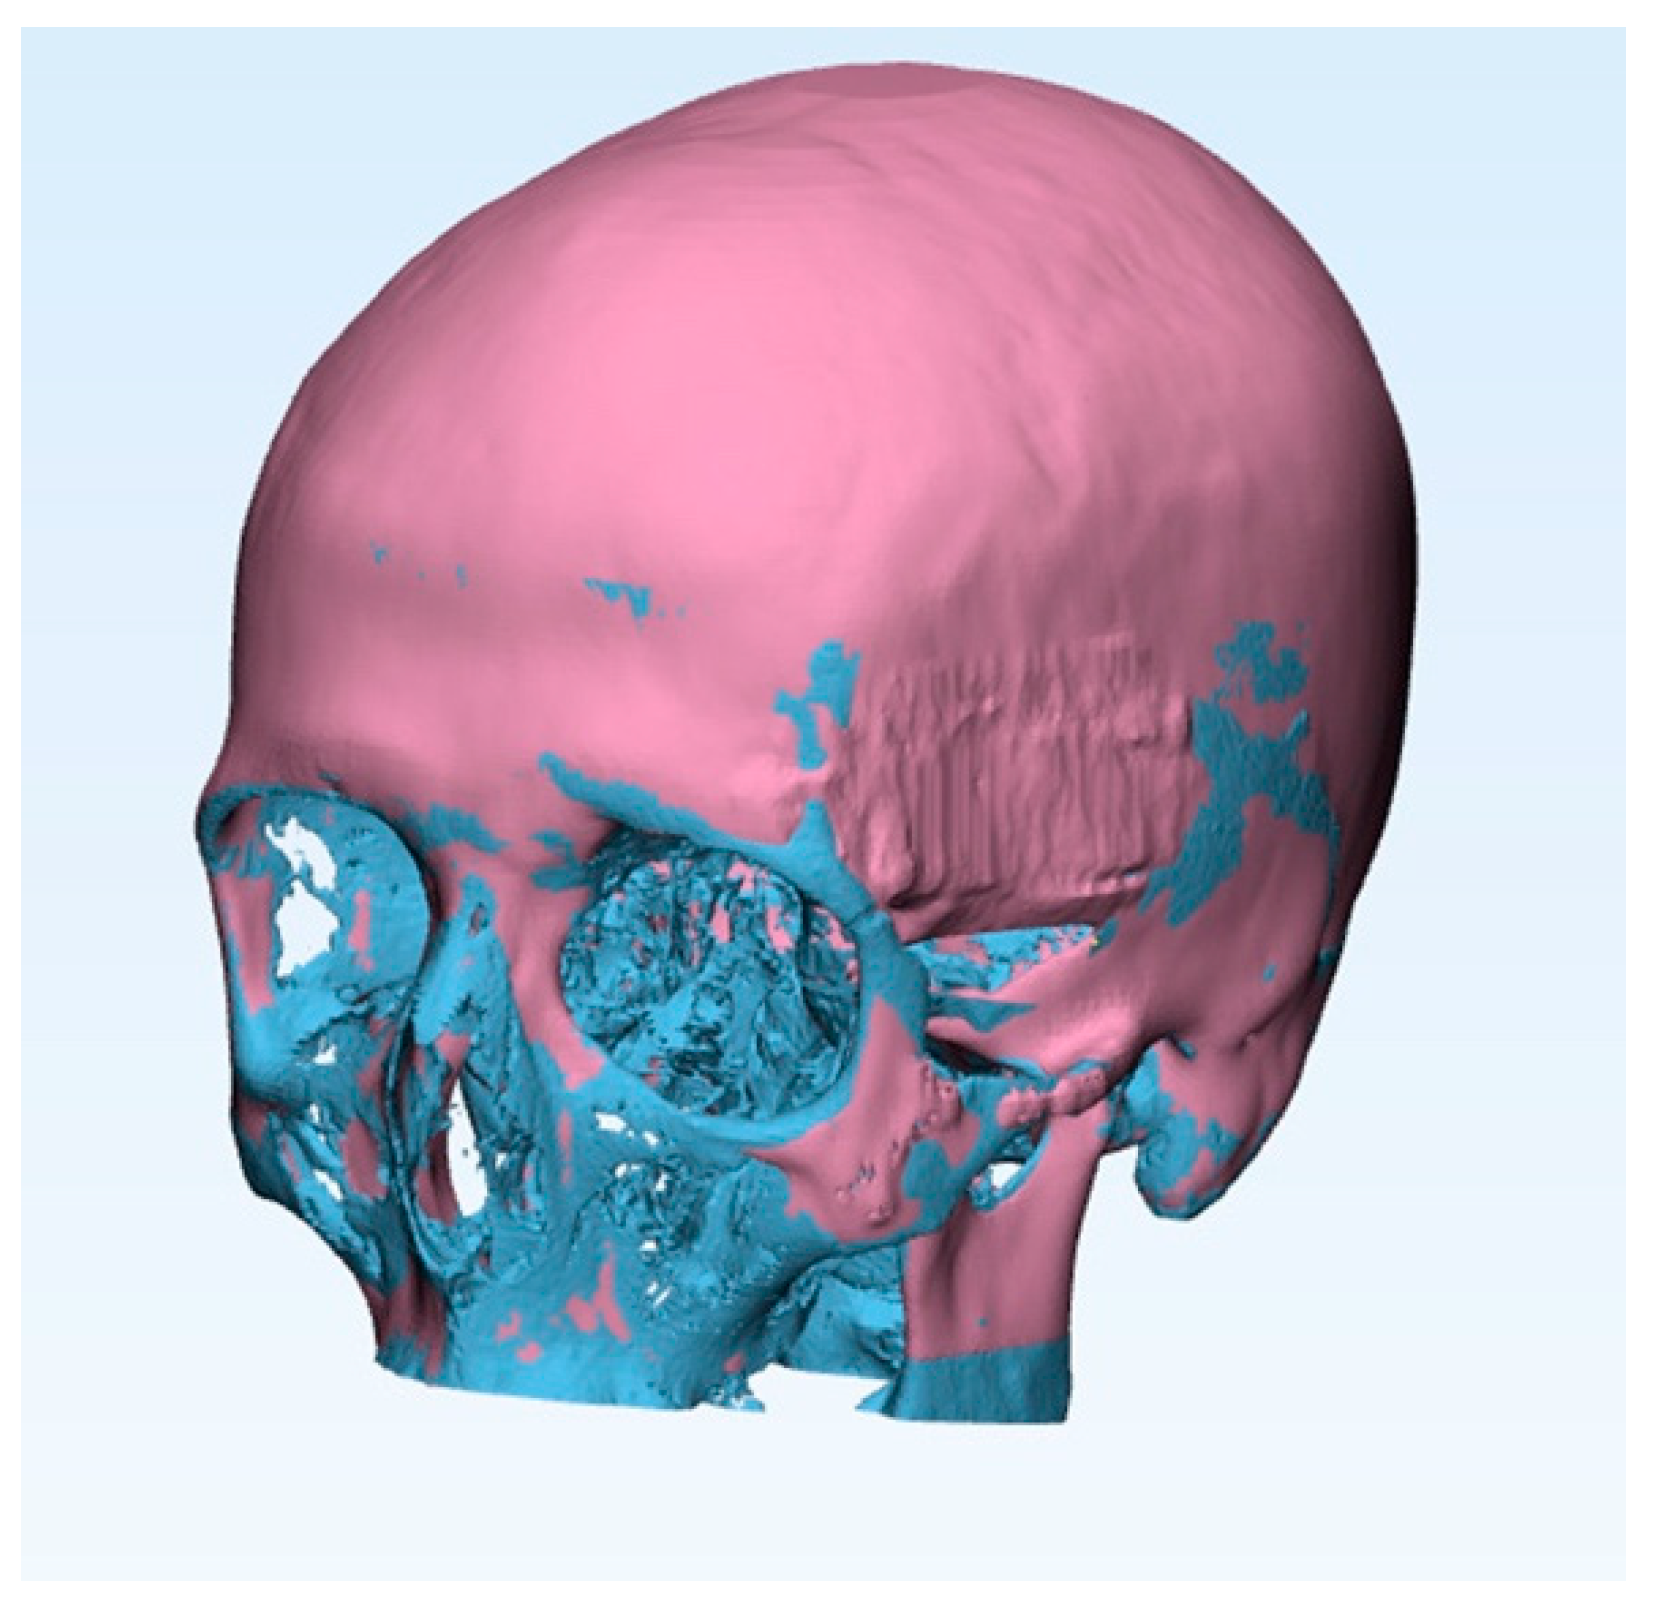

The other method used to evaluate the volumetric bone growth is the Boolean subtraction between the two solid models. The software that carries out the subtraction is 3-Matic Medical (Materialise). With 3-Matic, the Boolean subtraction is performed on the 3D models obtained starting from two CT scans: one before the surgery and the other one always at least 6 months after the surgery. After an automatic alignment, the models obtained from the CT scan before surgery is subtracted from the model obtained from the CT scan after surgery. The software shows the remaining volume, which coincides with the bone regenerated (Figure 3).

Figure 3.

Example of the pre-operative model imported as a mesh file (in gray) and the post-operative template imported as a CAD body file (in blue).